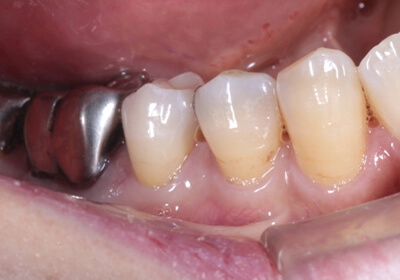

Case 02インプラント

モノリシックジルコニア